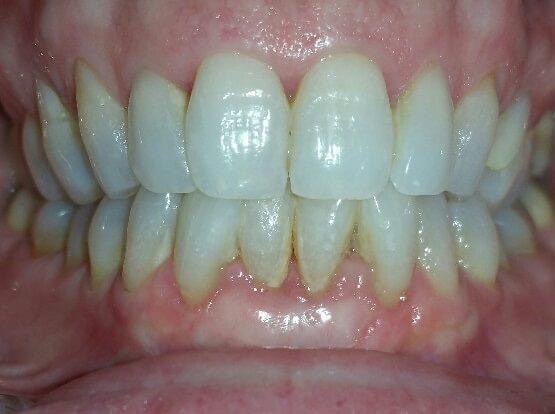

BEFORE AND AFTER PICTURES: